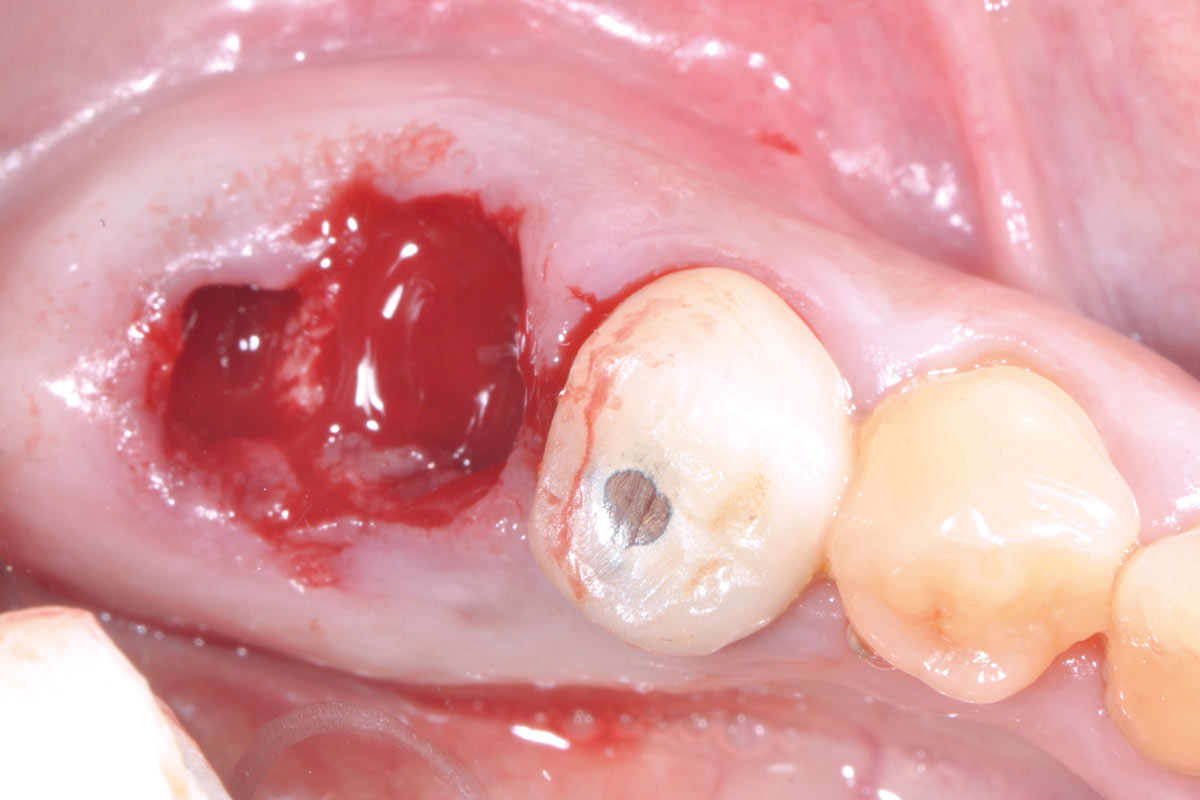

03/14 - Clinical situation after tooth extractionSocket preservation with maxresorb® and mucoderm® - Dr. M. Frosecchi

Alveolar socket before soft and hard tissue augmentation